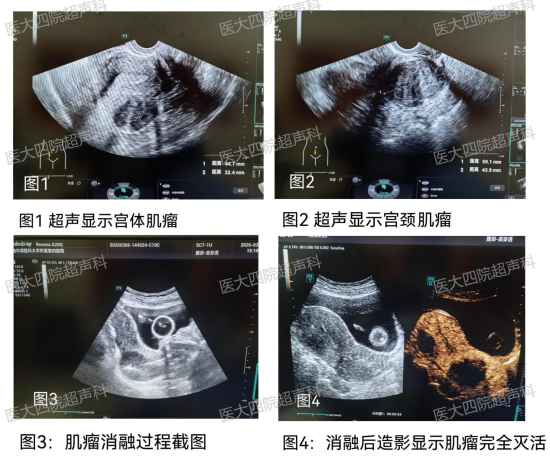

面对李女士复杂的情况——位于宫颈位置约60mm的肌瘤和宫体约45mm的肌瘤,位置刁钻。荆慧主任团队经过严谨的术前评估和精准的规划,为她量身定制了一套“双途径联合射频消融”的微创治疗方案。

在实时超声的精准引导下,仅用一根直径仅1.4mm的消融针,首先选择经腹部路径,精准穿刺并消融宫体的肌壁间肌瘤;随后,调整消融针路径,通过经阴道路径,直面位置刁钻的宫颈肌瘤,进行精准消融。手术过程顺利,全程不开刀、无切口、出血极少。李女士对治疗效果给予高度认可,露出了久违的笑容。

荆慧主任介绍,消融就像一场 “精准的体内狙击战”。通过射频产生的高温,让肌瘤细胞在瞬间发生不可逆的凝固坏死,“烧死”肿瘤,而周围的正常子宫组织则毫发无损。被灭活的肌瘤将不再继续生长,而是随着时间推移,被人体逐渐吸收、变小。